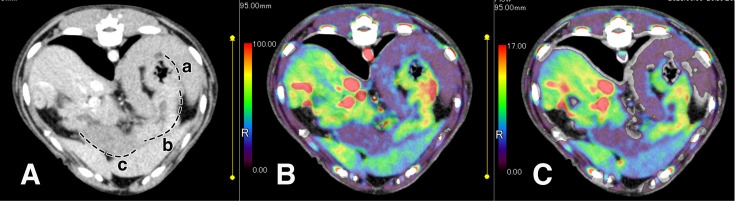

This study aimed to determine the feasibility of using perfusion computed tomography (CT) to assess blood flow in different regions of the stomach in dogs. Dynamic perfusion CT scans were conducted on five beagle dogs, and blood flow analysis was performed using the maximum slope and Patlak plot methods. The findings revealed significant variations in blood flow among the fundus, body, and pylorus of the stomach. Specifically, the body showed approximately 1.3 times higher blood flow than the fundus and approximately 5 times higher blood flow than the pylorus. There were no significant differences in blood flow between the two analysis algorithms. The findings suggest that gastric perfusion CT can accurately detect variations in blood flow within the stomach. Using the maximum slope method for analysis allows for noninvasive and rapid measurement of gastric blood flow. This technique may have clinical applications in detecting submucosal diseases that are challenging to identify with endoscopies and serve as a valuable noninvasive tool for longitudinal observations in experimental animal studies.

Abstract Image